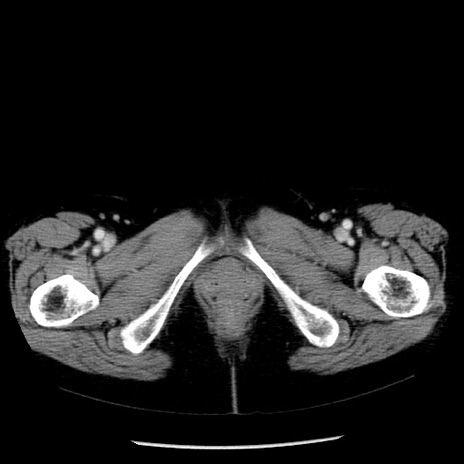

冠状断像